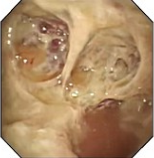

近年来,贵州航天医院各科室紧跟医学前沿,不断强技术、补短板,大力开展新技术、新项目,完成了许多高精尖、高难度、本地区“首例”的技术,填补了医院医疗技术空白,满足了群众日益增长的医疗需求。 贵州航天医院呼吸与危重症医学科是贵州省内呼吸疾病治疗规模最大,诊疗项目最全的呼吸疾病品牌科室,呼吸介入技术达到了全国先进水平,在贵州省内处于领先的地位。 本期,我们将为大家带来呼吸与危重症医学科特色技术——内科胸腔镜技术诊断和治疗胸腔疾病。 案例分享 患者苟某某,因劳累、气促,不明原因胸腔积液在某县一医院采取反复抽水等治疗手段效果不佳,当地医院考虑到患者年龄大(77岁),基础疾病较多,病情复杂,结合当地诊疗水平能力情况,建议转到上一级医院诊治,通过我院与该院建立的呼吸专科联盟绿色通道转入了我院。 患者入院后,呼吸与危重症医学科第一时间复查胸部CT,提示:右肺中叶、左肺感染,纤维化灶,左侧中量胸腔积液,右后侧胸膜轻度增厚,心包少量积液;并完善心电图、血常规、凝血功能、生化指标等术前检查。经科室专家团队集体讨论,得出患者左侧胸腔积液可能原因:结核?恶性?其他?冠心病、心功能不全、高血压病3级(高危组)、陈旧性肺结核复发?肺部感染;为进一步明确诊断,在充分评估、做好术前准备及应急预案、与患者及家属沟通的情况下,决定为患者进行内科胸腔镜检查术。 科室在患者入院第3天便实施了内科胸腔镜检查术,经检查取活检,病理不排除胸膜间皮瘤,送遵义医科大学附属医院病理会诊后诊断:胸膜间皮瘤。明确诊断后,科室专家团队为患者制定了个体化的治疗方案,患者病情很快得到有效控制,最终满意出院。半年后,医院通过电话回访,患者病情稳定,生活质量明显改善。 什么是内科胸腔镜 内科胸腔镜(medical thoracoscopy,MT)是一项微创诊断和治疗胸腔疾病的重要技术。主要应用于无创方法不能确诊的胸腔积液和胸膜疾病,通过局部麻醉后在胸壁做一个小切口,插入胸腔镜,直接观察胸膜、肺表面、纵隔等部位的病变情况,可进行活检、粘连松解及胸膜固定等操作。具有创伤小、恢复快、诊断准确性高等优点。 内科胸腔镜原理 内科胸腔镜是一项利用现代光学技术和成像技术的侵入性操作技术,应用电子支气管镜、硬质或软硬结合(半硬)的胸腔镜的一种电子内窥镜,末端装有连接着显示屏的微型摄像头。通过胸壁1-2cm左右的小切口,将内科胸腔镜及专用器械(戳卡套管)通过小切口进入胸腔,微型摄像头将胸腔内的情况投射到显示屏幕上,医生可以通过镜头全面、直观地观察患者胸腔内情况,了解胸膜病变确切位置和形态改变,还可对胸膜上的病变进行活检及治疗的操作技术,安全、微创、几乎无痛地“揭秘”不明原因的胸腔积液。 内科胸腔镜技术优势 (一)安全性高:仅需局部浸润麻醉,并发症发生率相对较低,对患者的身体条件要求较低。 (二)操作简便:操作时间短,痛苦少,患者耐受好。 (三)微创性:切口小,对患者身体损伤小,术后疼痛轻,恢复快。 (四)高分辨率成像:清晰显示胸腔内细微病变,提高诊断准确性。 (五)可直视操作:直接观察病变,进行精准活检和治疗。 (六)适用范围广:可用于不明原因胸腔积液、胸膜疾病、肺部疾病等的诊断和治疗。 (七)费用低:与外科胸腔镜比较费用低廉。 内科胸腔镜技术是贵州航天医院呼吸专科和呼吸介入诊疗优势的一部分,在2016年率先开展了内科胸腔镜技术,年手术量约100余例,已建立了快速、精准、规范、有效的一体化诊疗服务体系。目前呼吸与危重症医学科内科胸腔镜技术广泛应用于不明原因胸腔积液、气胸、脓胸的诊断和肺癌、弥漫性恶性胸膜间皮瘤等的分期,恶性或复发性胸腔积液、早期脓胸、自发性顽固性气胸的治疗。 镜下常见表现:单发或多发结节、灰白色弥漫性粟粒样结节、胸膜充血、水肿、胸膜增厚及纤维分隔或粘连带形成。 诊断方面: 胸腔积液的病因诊断。内科胸腔镜对恶性胸腔积液的诊断率可高达90%以上,胸腔镜对结核性病变诊断率极高,几乎达到96%以上。 腺 癌 恶性淋巴瘤 软骨肉瘤胸膜转移 滑膜肉瘤胸膜转移 结核性胸膜炎 治疗方面: 脓胸 肺大泡 贵州航天医院 呼吸与危重症医学科学科带头人 廖江荣 国务院政府特殊津贴专家 二级教授 主任医师 贵州航天医院副院长 国家级学术任职: 第二届中国医药教育协会介入微创专业委员会呼吸分会副主任委员 中国抗癌协会肿瘤微创治疗专业委员会常务委员 中国防痨协会结核病转化医学专业分会常务委员 第一届中国人体健康科技促进会呼吸介入专委会常务委员 中国医疗保健国际交流促进会结核病学分会第三届委员会常务委员 中国抗癌协会肿瘤微创治疗专业委员会粒子治疗学组第四届委员会委员 中华医学会结核临床专业委员会内镜介入委员 中华医学会放射学分会第十五届委员会介入学组呼吸系统介入专业委员会委员 北京健康促进会中青年专家委员会胸部疾病精准活检分委会副主任委员 中国医师协会介入医师分会第二届委员会肿瘤消融专业委员会委员 中国结核病防治综合质量控制专家指导委员会委员 亚洲冷冻治疗学会常务委员 世界内镜医师协会呼吸内镜协会常务理事 内镜临床诊疗质量评价专家委员会委员 “西部呼吸介入联盟”副理事长 专业擅长: 贵州航天医院 呼吸与危重症医学科简介 贵州航天医院呼吸与危重症医学科以呼吸危重症和介入呼吸病学为强力推手,以肺部感染性疾病及肺癌、肺小结节的早期精准诊疗、慢性呼吸疾病康复治疗为特色,以人才团队建设为核心的科室发展模式,现已成为省内呼吸疾病治疗规模最大,诊疗项目最全的呼吸疾病品牌科室。是贵州省医学重点学科、临床医学重点专科建设单位,遵义市首批呼吸重点学科、重点专科建设单位。是国家卫健委能力建设和继续教育肿瘤微创介入建设中心、贵州省县级医院微创介入培训中心、遵义市呼吸疾病临床医学中心。是国家呼吸医疗质量控制与管理哨点医院、遵义市呼吸内科专业医疗质量控制中心。是中国医药教育协会介入微创呼吸分会呼吸介入技术培训中心单位;国家卫健委海医会呼吸分会ROSE专委会“诊断性介入肺脏病学快速现场评价”培训基地;中国肺癌防治联盟“贵州航天医院肺结节诊治”分中心,中国人体健康科技促进会呼吸介入技术培训基地,贵州省中西医结合会呼吸学分会呼吸介入专委会主委单位。 基本情况 平均每年开展气管镜诊疗约4000例,经皮肺穿刺介入诊疗近千例,开展的项目包括经支气管镜(软、硬)下冷冻、氩气刀、高频电刀、球囊扩张、支架置入、超声内镜诊疗等气道介入诊疗技术,经皮肺穿刺活检及肿瘤消融术(微波、冷冻)、ROSE技术、内科胸腔镜诊疗及经血管介入诊疗技术,且多项呼吸介入诊疗技术在省内处于领先水平。 诊疗范围 航天医院呼吸专科擅长:致力于呼吸系统感染性、疑难性疾病的介入快速精准诊疗;肺癌与肺小结节早期精准诊疗水平项目提升。擅长于呼吸系统(肺)疑难病的诊断及危重病的救治,尤其在肺癌、肺小结节的早期诊断;肺癌综合靶向治疗;肺结核综合诊疗;肺部疾病的介入诊疗在省内处于前沿水平。 咨询热线 (一)呼吸与危重症医学科一病区 医生办公室:27677317 护士站:28614217 (二)呼吸与危重症医学科二病区 医生办公室:28691274 护士站:28690442 (三)呼吸与危重症医学科三病区 医生办公室:28692417 护士站:28690461 (四)呼吸与危重症医学科四病区 医生办公室:28616402、27677582 护士站:28614987、27677862